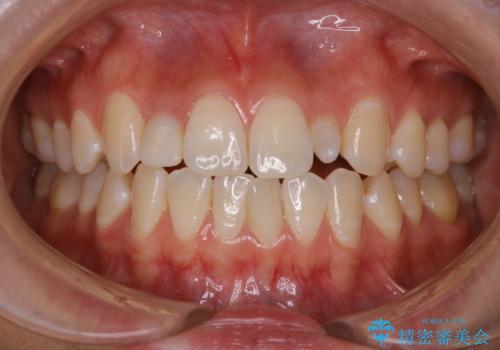

前歯のセラミックを作る前にホワイトニング

- 前歯のセラミッククラウンの型取りの前に、ホワイトニングで全体を白くしたいとのことでした。オフィスホワイトニングのエクセレントコース・トリートメントを行いました。